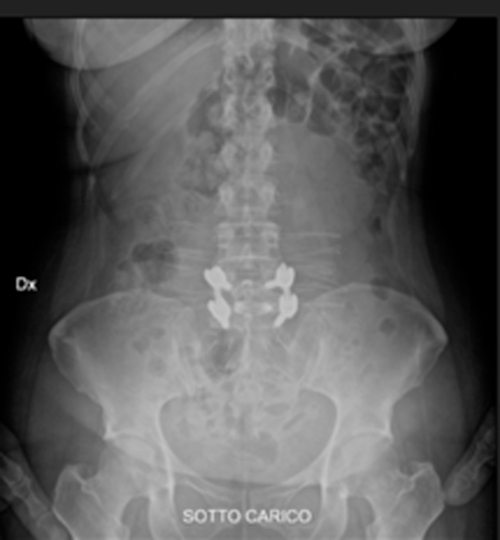

SPONDILOLISTESI CON STENOINSTABILITA’ L3-L5

Radiografia lombare pre-operatoria